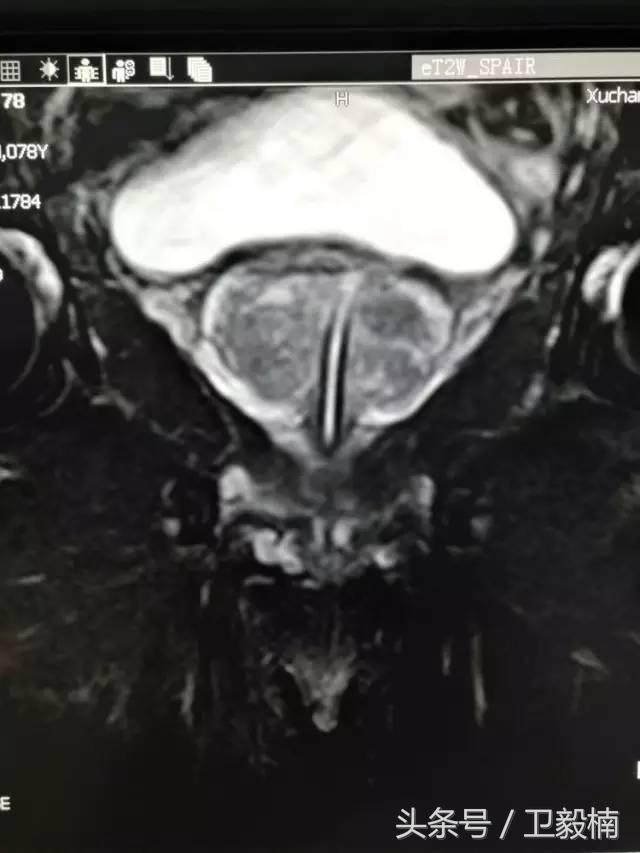

七、子宫肌瘤、子宫腺肌症、宫外孕、输卵管阻塞引起的不孕症等妇产科疾病;